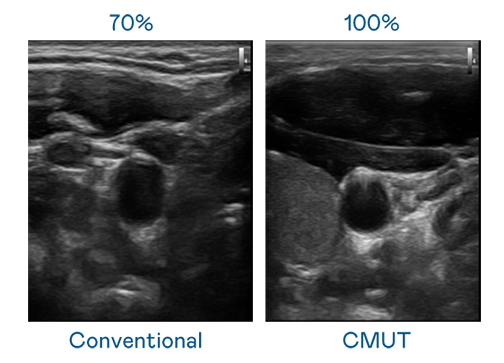

CMUT 技术是一种用电容式微机电元件来产生超音波讯号的技术。与传统 PZT 压电式技术相比,CMUT 频宽增加 3友达%,更宽频的超音波讯号让影像解析度大幅提升,是实现高影像品质医疗超音波扫描、促进精准医疗发展的关键技术。

超音波影像的解析度高低,首先取决于探头能发出的讯号频宽。友达 CMUT 可提供高清晰的超音波讯号,提供高频宽、高灵敏度、影像纹理细节更高的超音波影像,协助医护人员缩短影像判读时间及利用精准的医疗影像进行诊断。